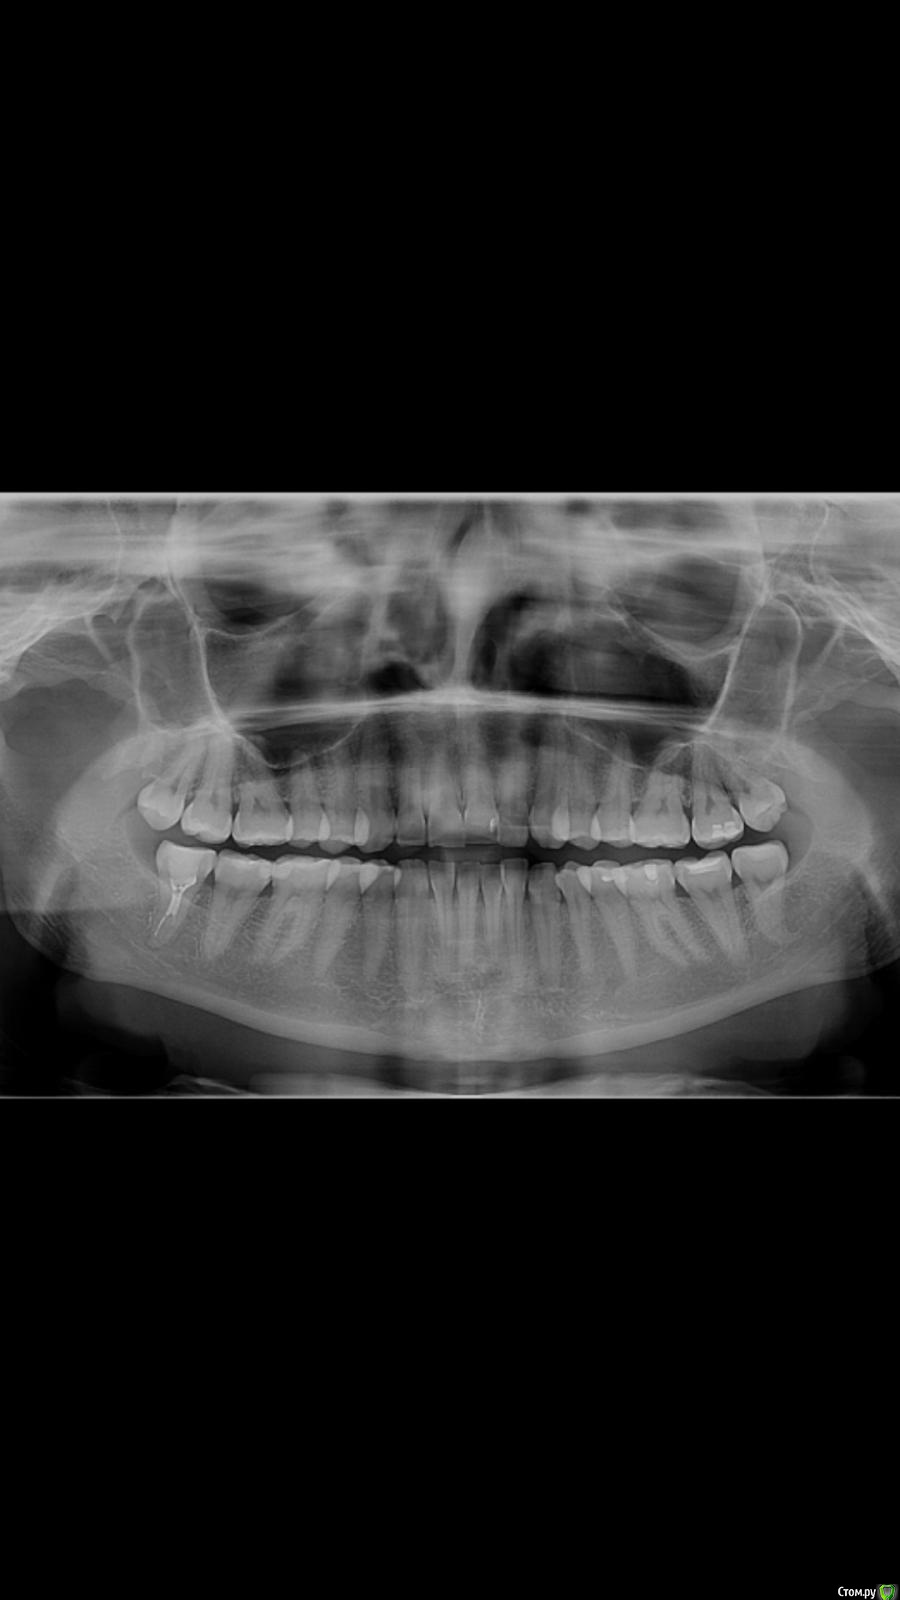

enka Опубликовано 30 января, 2020 Поделиться Опубликовано 30 января, 2020 Здравствуйте, уважаемые доктора! Подруга КОРМЯЩАЯ стал ныть зуб (восьмерка снизу), снимок показал не до конца пролеченный канал. Доктор вскрыл, прочистил, промыл каким-то раствором и под временной пломбой отправил домой, сказав, что кормящим антибиотики нельзя! Зуб на четвертые сутки стал ныть, ощутим при жевании. К доктору в воскресенье. Вопрос....действительно ли ничего антибактериального нет для кормящих и как быть, если боль не пройдет? Ссылка на комментарий

enka Опубликовано 30 января, 2020 Автор Поделиться Опубликовано 30 января, 2020 (изменено) Фото только такое. До лечения! Изменено 30 января, 2020 пользователем enka Ссылка на комментарий

enka Опубликовано 30 января, 2020 Автор Поделиться Опубликовано 30 января, 2020 Фото только такое. Ссылка на комментарий